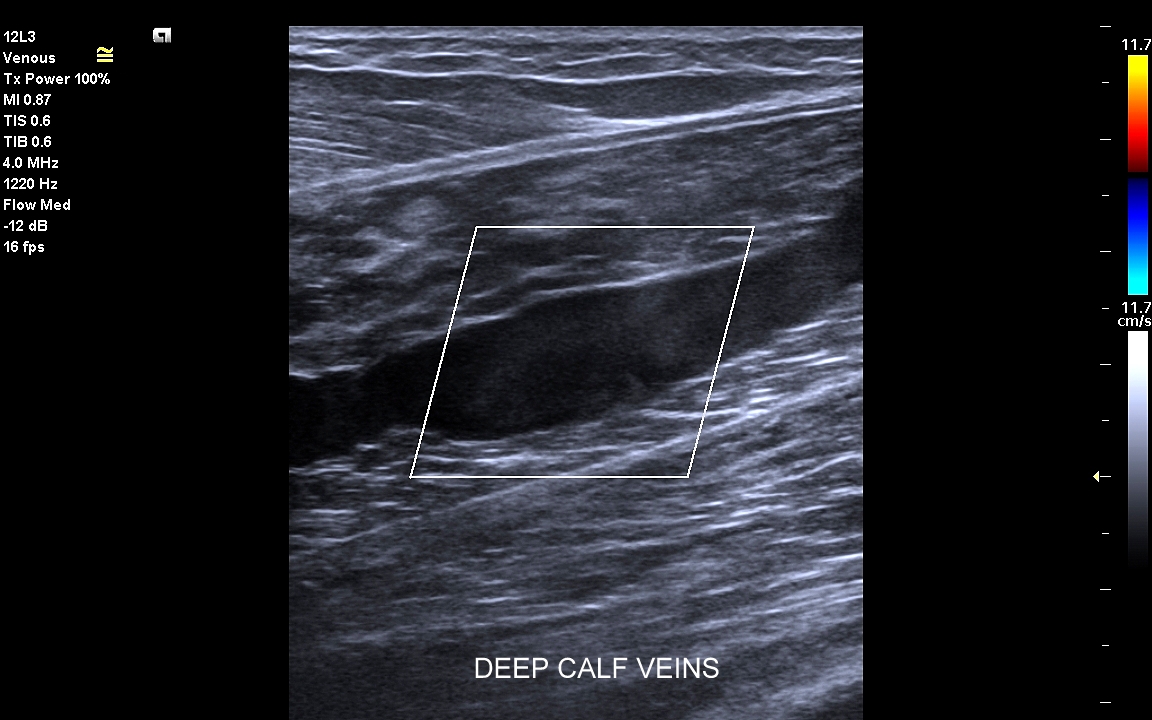

• zakrzepica żył głębokich kończyn dolnych;

Czym jest zakrzepica żył? Zakrzepica żylna polega na powstaniu skrzepu wewnątrz naczynia żylnego i wtórnym rozwoju stanu zapalnego w okolicy naczynia. Choroba dotyczyć może układu powierzchownego żył lub żylaków, a w tym wypadku nie jest zwykle stanem niebezpiecznym; a także układu głębokiego żył, co z kolei jest stanem potencjalnie zagrażającym życiu, gdyż może sprowokować zatorowość płucną. Zakrzepica żył głębokich (ang. deep venous thrombosis DVT) częściej występuje w obrębie żył kończyn dolnych, następnie w obrębie żył biodrowych, rzadziej w żyle podobojczykowej i żyłach głębokich kończyny górnej. Przyczyny zakrzepicy żylnej są różnorodne i obejmują m. in. długie podróże, długotrwałe unieruchomienie, operacje ortopedyczne, chirurgiczne i szczękowe, urazy tkanek miękkich oraz złamania kości, genetycznie uwarunkowane trombofilie, nowotwory złośliwe, odwodnienie, infekcje miejscowe i ogólnoustrojowe. W przypadku zakrzepicy żyły podobojczykowej klasyczną jej przyczyną jest ucisk; w swojej praktyce klinicznej dr Szczepański spotkał się z zakrzepicą podobojczykową wywołaną m. in. przez ciężki plecak, wyciskanie sztangi na siłowni, czy przez uprawianie wspinaczki skałkowej. W warunkach szpitalnych zakrzepica żyły podobojczykowej lub żyły szyjnej wewnętrznej może pojawić się w wyniku zakładania cewników dożylnych. Sprawne wykrycie zakrzepicy w badaniu USG, a następnie wdrożenie odpowiedniej terapii uchronić może pacjenta przed powikłaniami ostrymi (np. zator płucny), jak i opóźnionymi (np. zespół pozakrzepowy).

USG Doppler żył kończyn dolnych

Badanie USG żył kończyn dolnych najczęściej wykonywane jest w ramach diagnostyki niewydolności żył powierzchownych oraz ich objawów w postaci pajączków żylnych, żylaków kończyn dolnych, obrzęków i owrzodzeń żylnych. Kolejnym pod względem częstości wskazaniem do badania Doppler żył jest podejrzenie zakrzepicy żył głębokich kończyn dolnych, monitorowanie leczenia zakrzepicy oraz ocena jej powikłań odległych. Powikłaniem nieleczonej zakrzepicy żył głębokich może być zespół pozakrzepowy manifestujący się masywnymi obrzękami kończyny i zaburzeniami troficznymi. Badanie USG Doppler żył kończyn dolnych często uzupełniane jest oceną układu żył centralnych w miednicy i jamie brzusznej. W tych obszarach również pojawiać się mogą żylne zmiany zakrzepowe, niedrożności żył, a nawet zmiany nowotworowe.

Czy USG Doppler wykrywa zakrzepicę? Tak, badanie Doppler żył jest najważniejszą metodą diagnostyczną wykrywającą zakrzepicę żył głębokich i powierzchownych. W związku z faktem, iż nieleczona zakrzepica żył głębokich może być przyczyną niebezpiecznego zatoru płucnego lub utraty kończyny badanie Doppler należy wykonać jak najszybciej w każdym przypadku podejrzenia zakrzepicy.